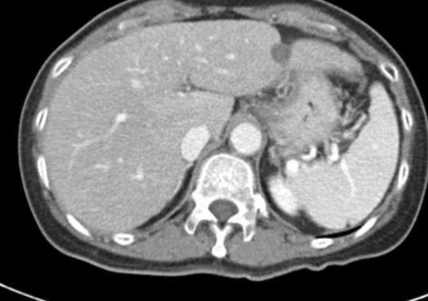

肝左叶肝细胞肝癌射频消融术后一年,病灶表现为弱强化,邻近肝包膜皱缩。

肝右叶肿瘤射频消融术后,邻近肝包膜皱缩。